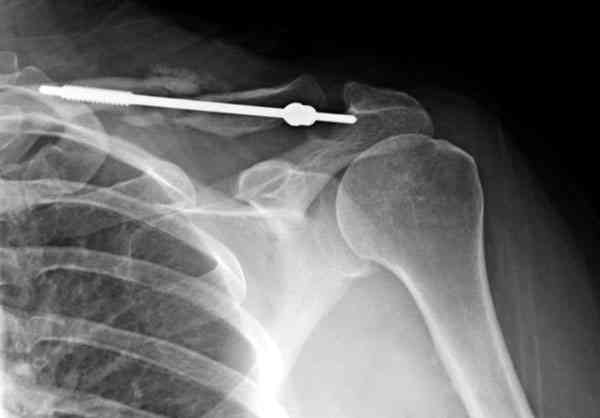

ГГШ> Результат стационарного лечения приведен на рентгенограмме (Xray_3).

Это картинка то есть через неделю после травмы, при выписке? Более чем приемлемо.

Оценка положения костных фрагментов должна осуществляться по рентгенограммам, вы.полненным в двух проекциях. Стандартная ( и почему.то считающейся достаточной в большинстве наших лечебных учреждений) передне.задняя проекция дополняется шейной проекций под уг.лом 45°. Смещения: расхождение в поперечном направлении, отсутствие кортикального контакта, укорочение ключицы более 1,5 см . недопустимы и должны быть устранены (11,12).

Уважаемая Г.В. Полностью согласен с Вашим постом.Закрытая репозиция и кольца Дельбе отлично зарекомендовали себя за 35 лет практики. В обсуждаемом случае представленные Р-граммы сами говорят за себя, 1 снимок (до лечения) и 3 снимок (после лечения) абсолютно идентичны, 2 снимок сделан в несколько иной позиции.Как говорится "комментарии излишни". Согласитесь, что результат лечения мог бы быть и лучшим.